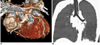

Fig. 1

Volume-rendered CT image with non-ECG-synchronized spiral scan shows excellent anatomic details of pulmonary arteries in 12-year-old girl with repaired coarctation of aorta.